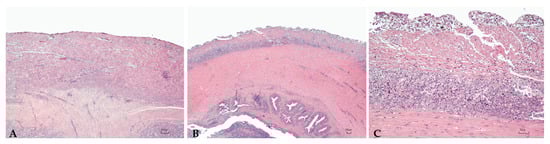

Sturgeons showed mild to severe granulomatous chronic inflammatory reactions ranging from mild to severe degrees in all examined organs. In particular, the hepatic parenchyma was expanded by multifocal to coalescing, multinodular, variable size granulomas mainly located near vessels and bile ducts and extended to the serosal surface in the most severe cases (Figure 1). Mild and diffuse congestion of blood vessels was observed in a single case with mild inflammation. The spleen was diffusely expanded in all sturgeons except in one specimen, by a mild to severe chronic granulomatous inflammation associated with edema and vascular congestion (Figure 2). In two out of four sturgeons, the serosa and the outer muscular layer of the small intestine were characterized by a diffuse granulomatous inflammation, whereas the mucosa and submucosa were unaffected (Figure 3). Results are summarized in Table 2.

Figure 3. Intestine. Mild (A) and severe (B,C) granulomatous chronic enteritis. (C): High magnification, Table 2. (B) showing a high number of activated macrophages located in the serosa and the outer muscular layer. H.E. Bar (AC) = 100 µm.

The previous paper of Mugetti et al. [28] showed clinical signs consistent with those ready reported regarding A. baerii [8] and A. transmontanus [25]. In this second episode two sturgeons were externally normal, even if the histopathological analysis reported a mild inflammation of the liver and the spleen; other two samples were instead characterized by starvation and skeletal deformities, as already reported for A. transmontanus [26]. Moreover, the multifocal involvement of the liver, spleen, and of the intestine mainly centered around vessels and bile ducts, indicating a systemic granulomatous inflammation, and was reported.